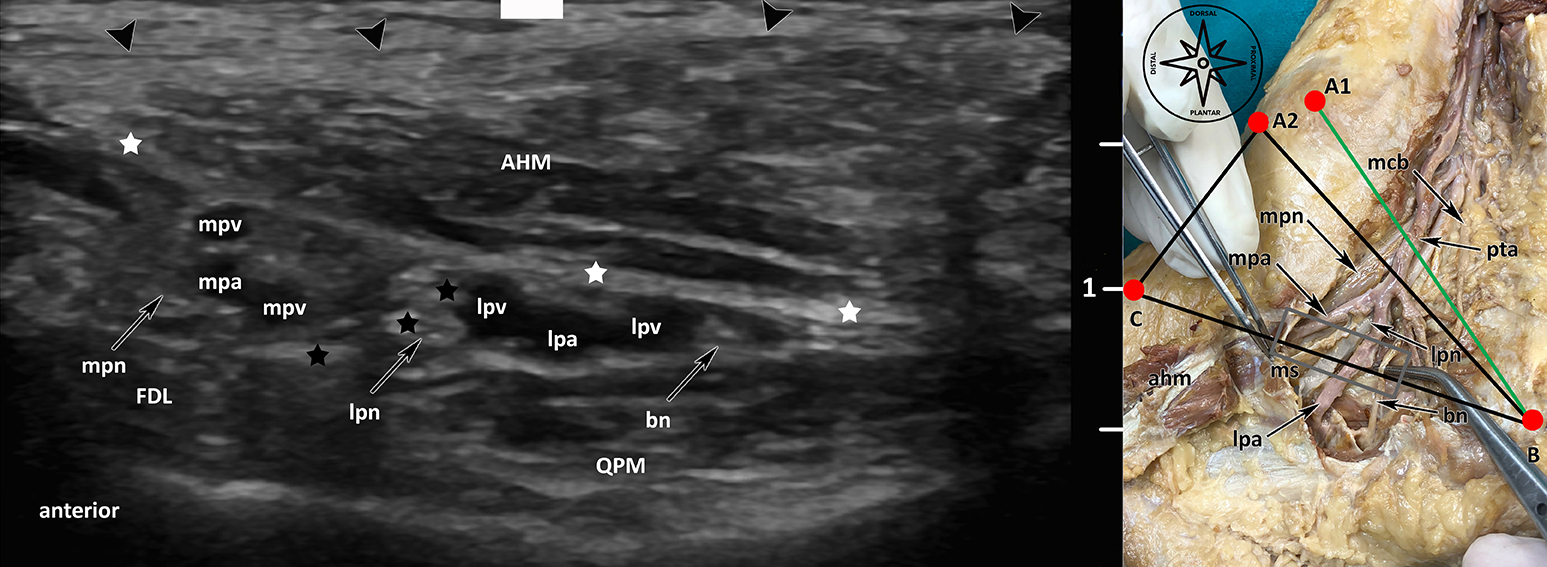

All our “Applied Anatomy” courses are delivered with the aim of developing new surgical approaches, improving modern imaging techniques and finding new applications for clinical practice (Fig. 1, Fig. 2).

Furthermore, new, minimally invasive approaches for various peripheral nerve compression diseases are being investigated with the application of ultrasound, e.g. tarsal tunnel syndrome and carpal tunnel syndrome. As a result, patients receive a new, minimally invasive surgical method, in which decompression of the peripheral nerve can be achieved via a 2 mm approach only.

In the field of neurosonography, the main applications for clinical and preoperative practice are developed on body donors to science and on volunteers, in order to be able to apply the results to our patients immediately, e.g. in the field of interventional radiology and ENT as well as regional anaesthesia and pain therapy (Fig. 1, Fig. 2).